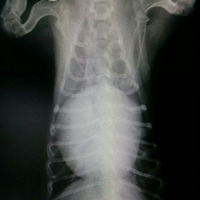

【心臓病|心肥大】早期の症状は咳です ~早期発見・早期治療が大事~

ここは『ハナちゃんの動物病院』(犬版)です。 今日は心臓病のお話ですよ。 ワンちゃんの病気はなかなか分かりにくいけれど、咳は心臓病のサインだったりします。心臓が肥大すると、気管を圧迫するから、咳がでちゃうんだって。 でも、咳が出たら必ず心臓病ってわけじゃないから、心配しすぎないでね。とにかく、妙な咳が…